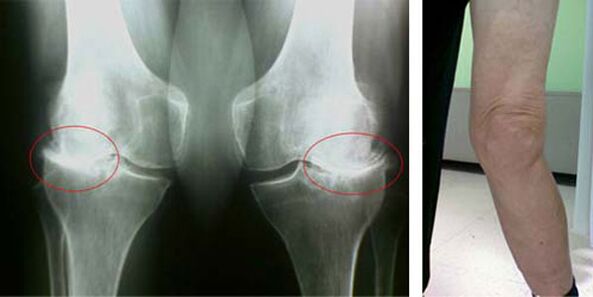

Nunha articulación sa do xeonllo, a cartilaxe é unha especie de revestimento que non permite que os ósos se toquen, polo que se elimina a posibilidade de danos ao camiñar. A cartilaxe enferma non pode facer fronte a esta función, polo tanto, aparecen signos de rixidez na articulación durante o movemento, acompañados de dor. Esta condición faise permanente debido a cambios patolóxicos internos, cando o adelgazamento do tecido da cartilaxe leva ao engrosamento do óso e crea condicións para a aparición de espolones óseos - osteofitos, que provocan dor aguda.

As fases iniciais da aparición dunha patoloxía como a artrose da articulación do xeonllo non se manifestan visualmente de ningún xeito. Non obstante, despois dun certo tempo, o paciente nota sinais de deformidade do xeonllo, así como unha curvatura característica ao longo do eixe da perna inferior (dirixido cara a dentro). Tamén hai unha crise cando necesitas dobrar a perna.

A presenza de dor, movemento limitado no xeonllo fai que unha persoa vexa un médico e se someta a un exame. Para iso, ten que pasar probas e facer unha radiografía da articulación enferma. Se estas medidas non son suficientes para confirmar a artrose da articulación do xeonllo, realízase unha resonancia magnética. En función dos datos recollidos, o médico elixe os mellores métodos de tratamento.